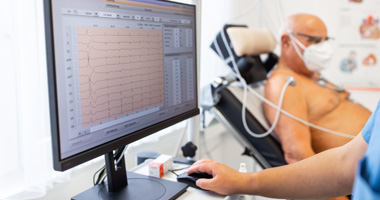

In many cases, cardiovascular diseases are “silent,” meaning they go unnoticed until a person begins to show symptoms of heart failure, a heart attack, or an arrhythmia.6 Some common ways heart conditions affect health, along with their symptoms, include:

- Heart attack: Chest pain, shoulder or arm pain, shortness of breath9

- Arrhythmia: Feeling faint, dizzy, tired, weak, or having trouble breathing10

- Heart failure: Difficulty breathing, lower-body swelling, shortness of breath with normal activity11